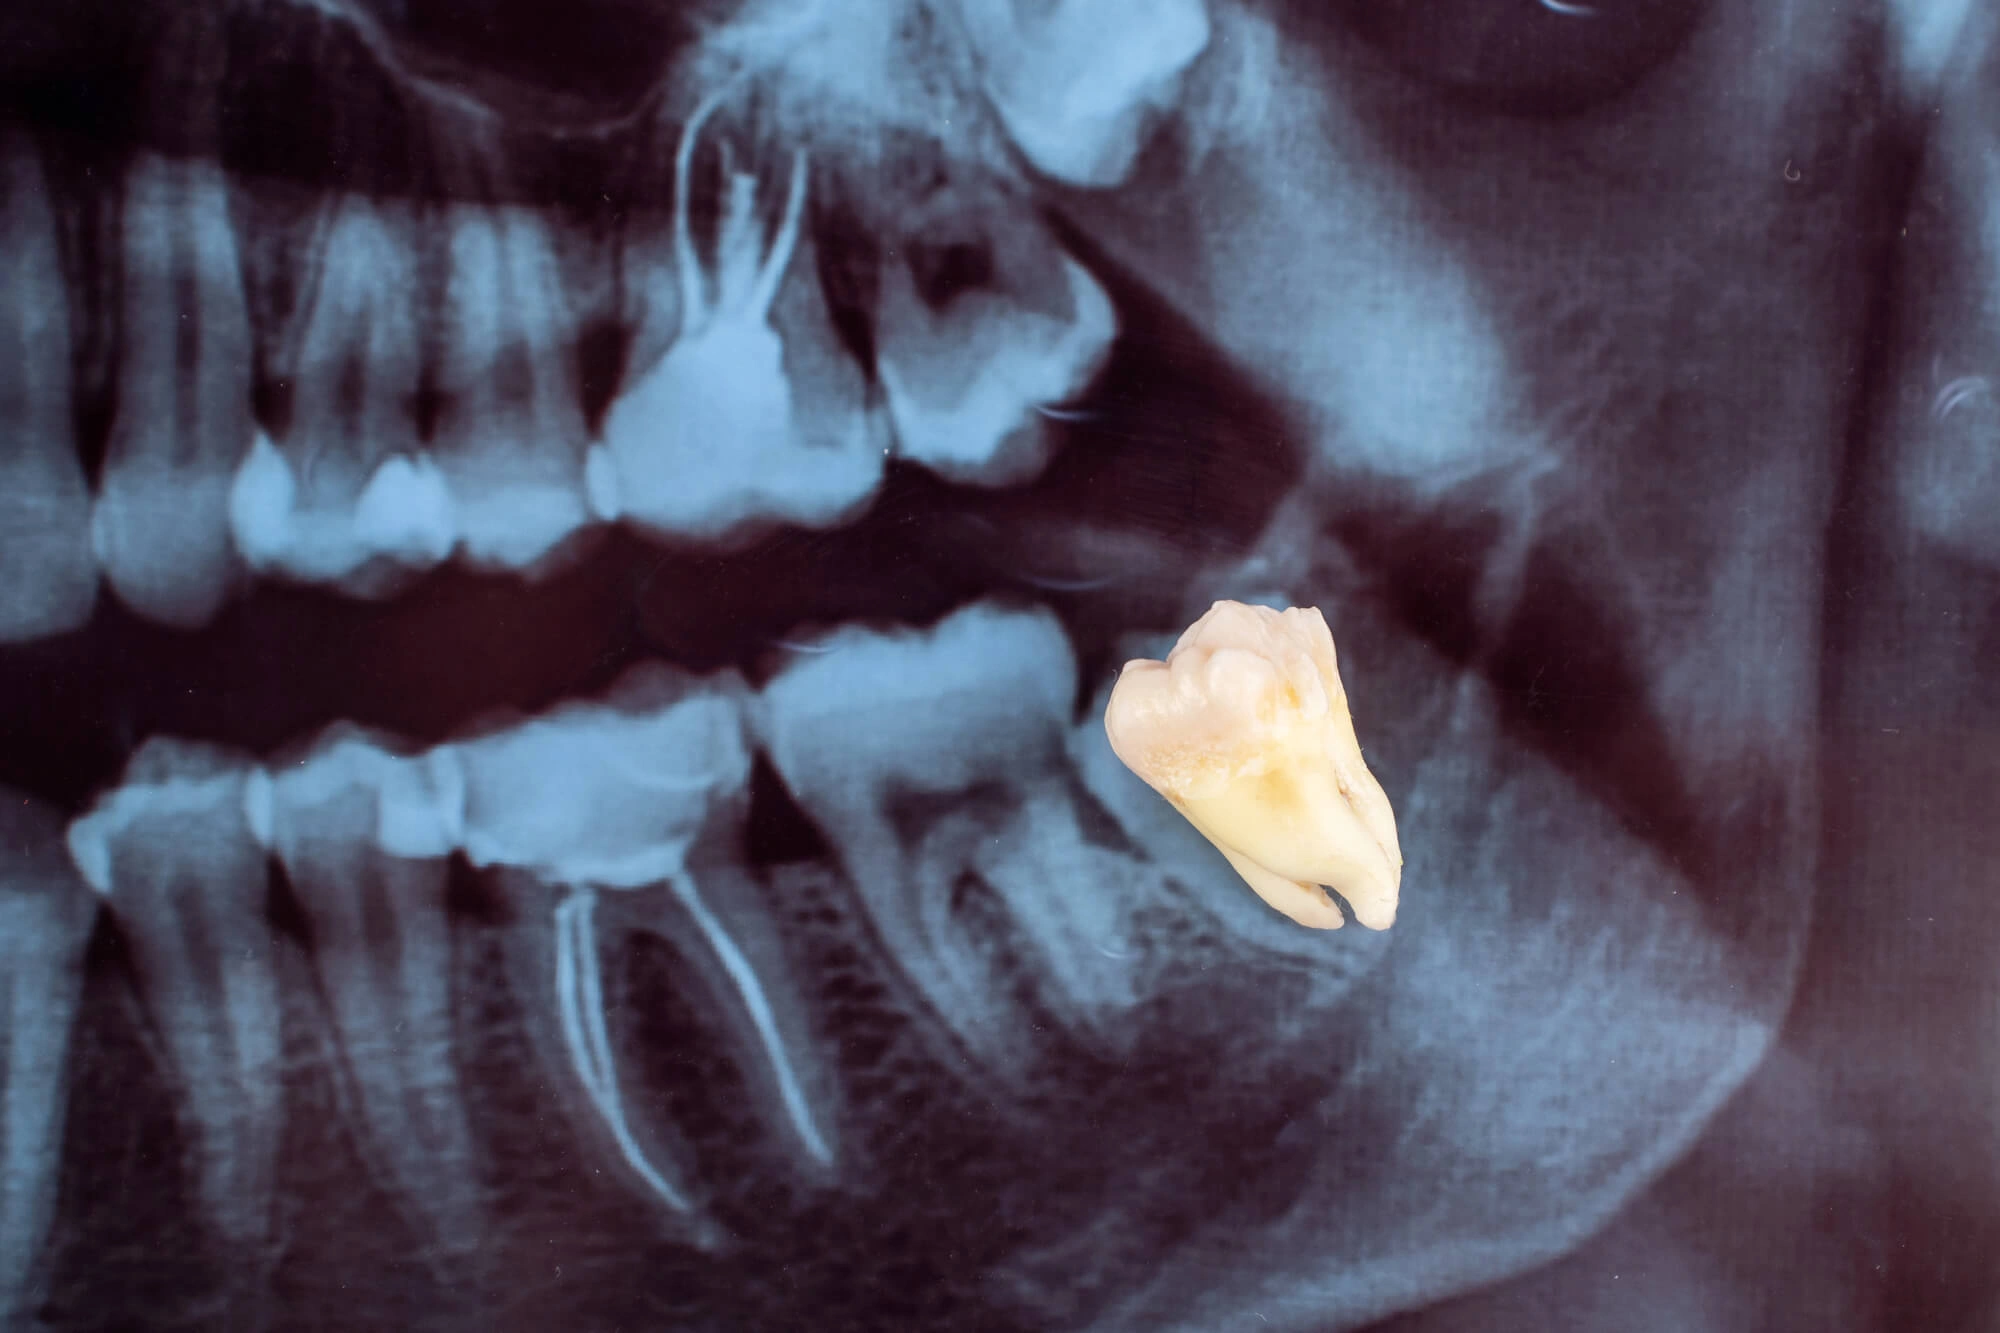

Wisdom teeth, also known as third molars, often emerge in early adulthood and may require a wisdom tooth extraction if they cause crowding, discomfort, or infection when not properly managed.

When wisdom teeth become impacted (trapped under the gums or bone), they can lead to more serious dental problems. Early removal helps prevent complications such as cysts, gum disease, and damage to adjacent teeth.

Wisdom teeth removal is a routine dental procedure performed under local anesthesia, sedation, or general anesthesia depending on the complexity. Your dentist or oral surgeon will carefully remove the tooth, sometimes in sections, to minimize impact on surrounding tissue.